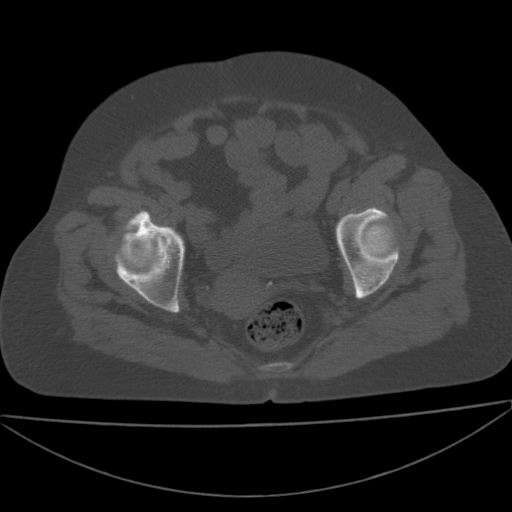

以下是引用王显瑞在2009-4-23 16:45:00的发言:[br]考虑股骨颈陈旧性骨折,股骨头缺血型坏死

以下是引用余辉在2009-4-23 17:08:00的发言:[br]考虑右髋关节退行性变.股骨颈改变考虑陈旧性骨折可能,股骨头顶部关节面下似有透亮区,股骨头皮质环增厚,考虑有股骨头坏死